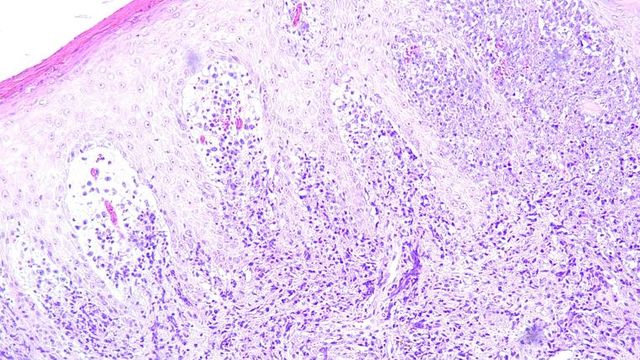

Histology slide showing tumor microenvironment cells under a microscope, illustrating insights for cancer treatment strategies.

Understanding the Tumor Microenvironment With a Precise Spatial Transcriptomics Platform

This poster highlights the importance of exploring the spatial organization of the entire transcriptome in cancer tissues and presents a powerful platform for unraveling the complexities of the TME.